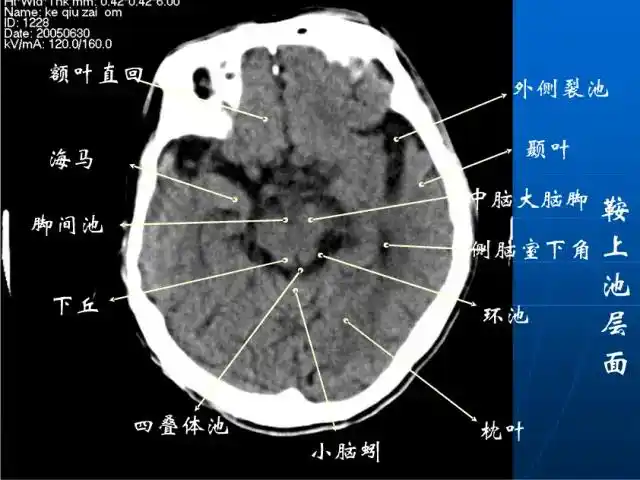

影像医生必须掌握的头颅ct解剖与常见出血梗死判读

头颅ct解剖与常见出血梗死判读

珍藏| 颅脑ct断面解剖彩色图谱